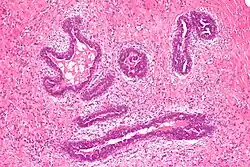

Microscopic image showing gynecomastoid hyperplasia, the cellular changes seen in gynecomastia H&E stain

Gynecomastoid hyperplasia - Low magnification

Early histological features expected to be seen on examination of gynecomastic tissue attained by fine-needle aspiration biopsy include the following: proliferation and lengthening of the ducts, an increase in connective tissue, an increase in inflammation, and swelling surrounding the ducts, and an increase in fibroblasts in the connective tissue.[26] Chronic gynecomastia may show different histological features such as increased connective tissue fibrosis, an increase in the number of ducts, less inflammation than in the acute stage of gynecomastia, increased subareolar fat, and hyalinization of the stroma.[24][26] When surgery is performed, the gland is routinely sent to the lab to confirm the presence of gynecomastia and to check for tumors under a microscope. The utility of pathologic examination of breast tissue removed from male adolescent gynecomastia patients has recently been questioned due to the rarity of breast cancer in this population.[57]